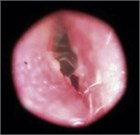

急性外耳道炎